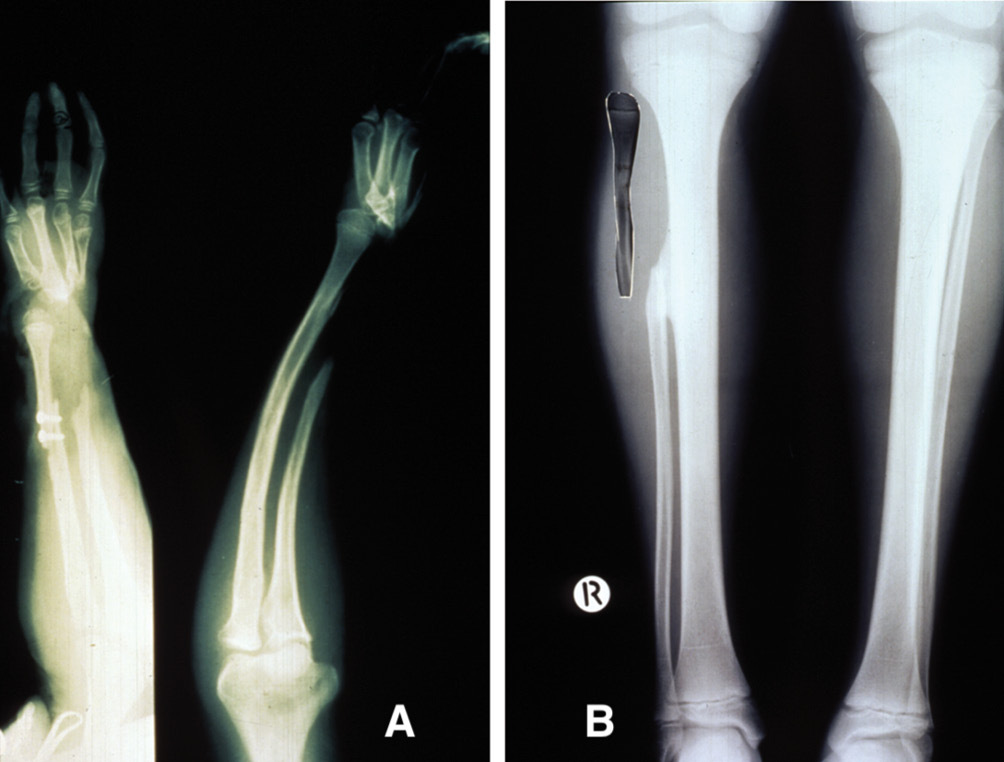

On 20 March 1982, a four-year-old boy sustained a severe compound injury to his left forearm and hand from a motor mower accident. Distal ends of the radius and ulna, and fifth metacarpal and carpal bones on the ulnar side of the hand were missing (Figure 13A). Treated initially by Tim Pitt, the hand was debrided and closed with a filleted fifth finger skin flap and stabilised with an external fixateur. Over the following six months, spontaneous regeneration of the distal radius was observed from residual periosteum that became incorporated with the distal epiphysis (Figure 13B). However, its growth plate had been destroyed, the forearm was short and the patient was referred to us by Tim Pitt for possible free vascularised growth plate transfer.

Bony union of the fibula to the radius was evident at six weeks. Serial X-rays of both forearms were made at three-monthly intervals over the next four years and the results confirmed with bone scans. These revealed an average growth rate of 5 mm per year of the fibula growth plate, which compared with that of the distal radial epiphysis in the opposite forearm (Figure 16A) and the proximal growth plate in the fibula of the normal left leg (Figure 16B).